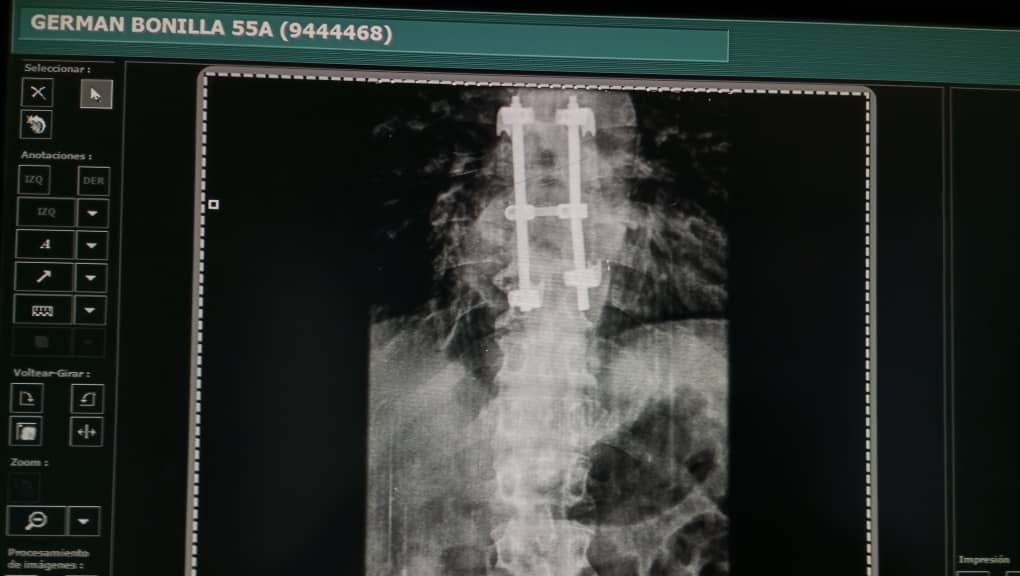

El pasado viernes 28 de julio le realizaron una Cirugia de columna, le colocaron ganchos estabilizadores en las vertebra T9 para asi evitar el desplome y hacerle un soporte a traves de los años.

On July 28th, he had spinal surgery where doctors placed stabiliazing hooks in his T9 vertebrae to avoid further damage and to build support over the years to come.